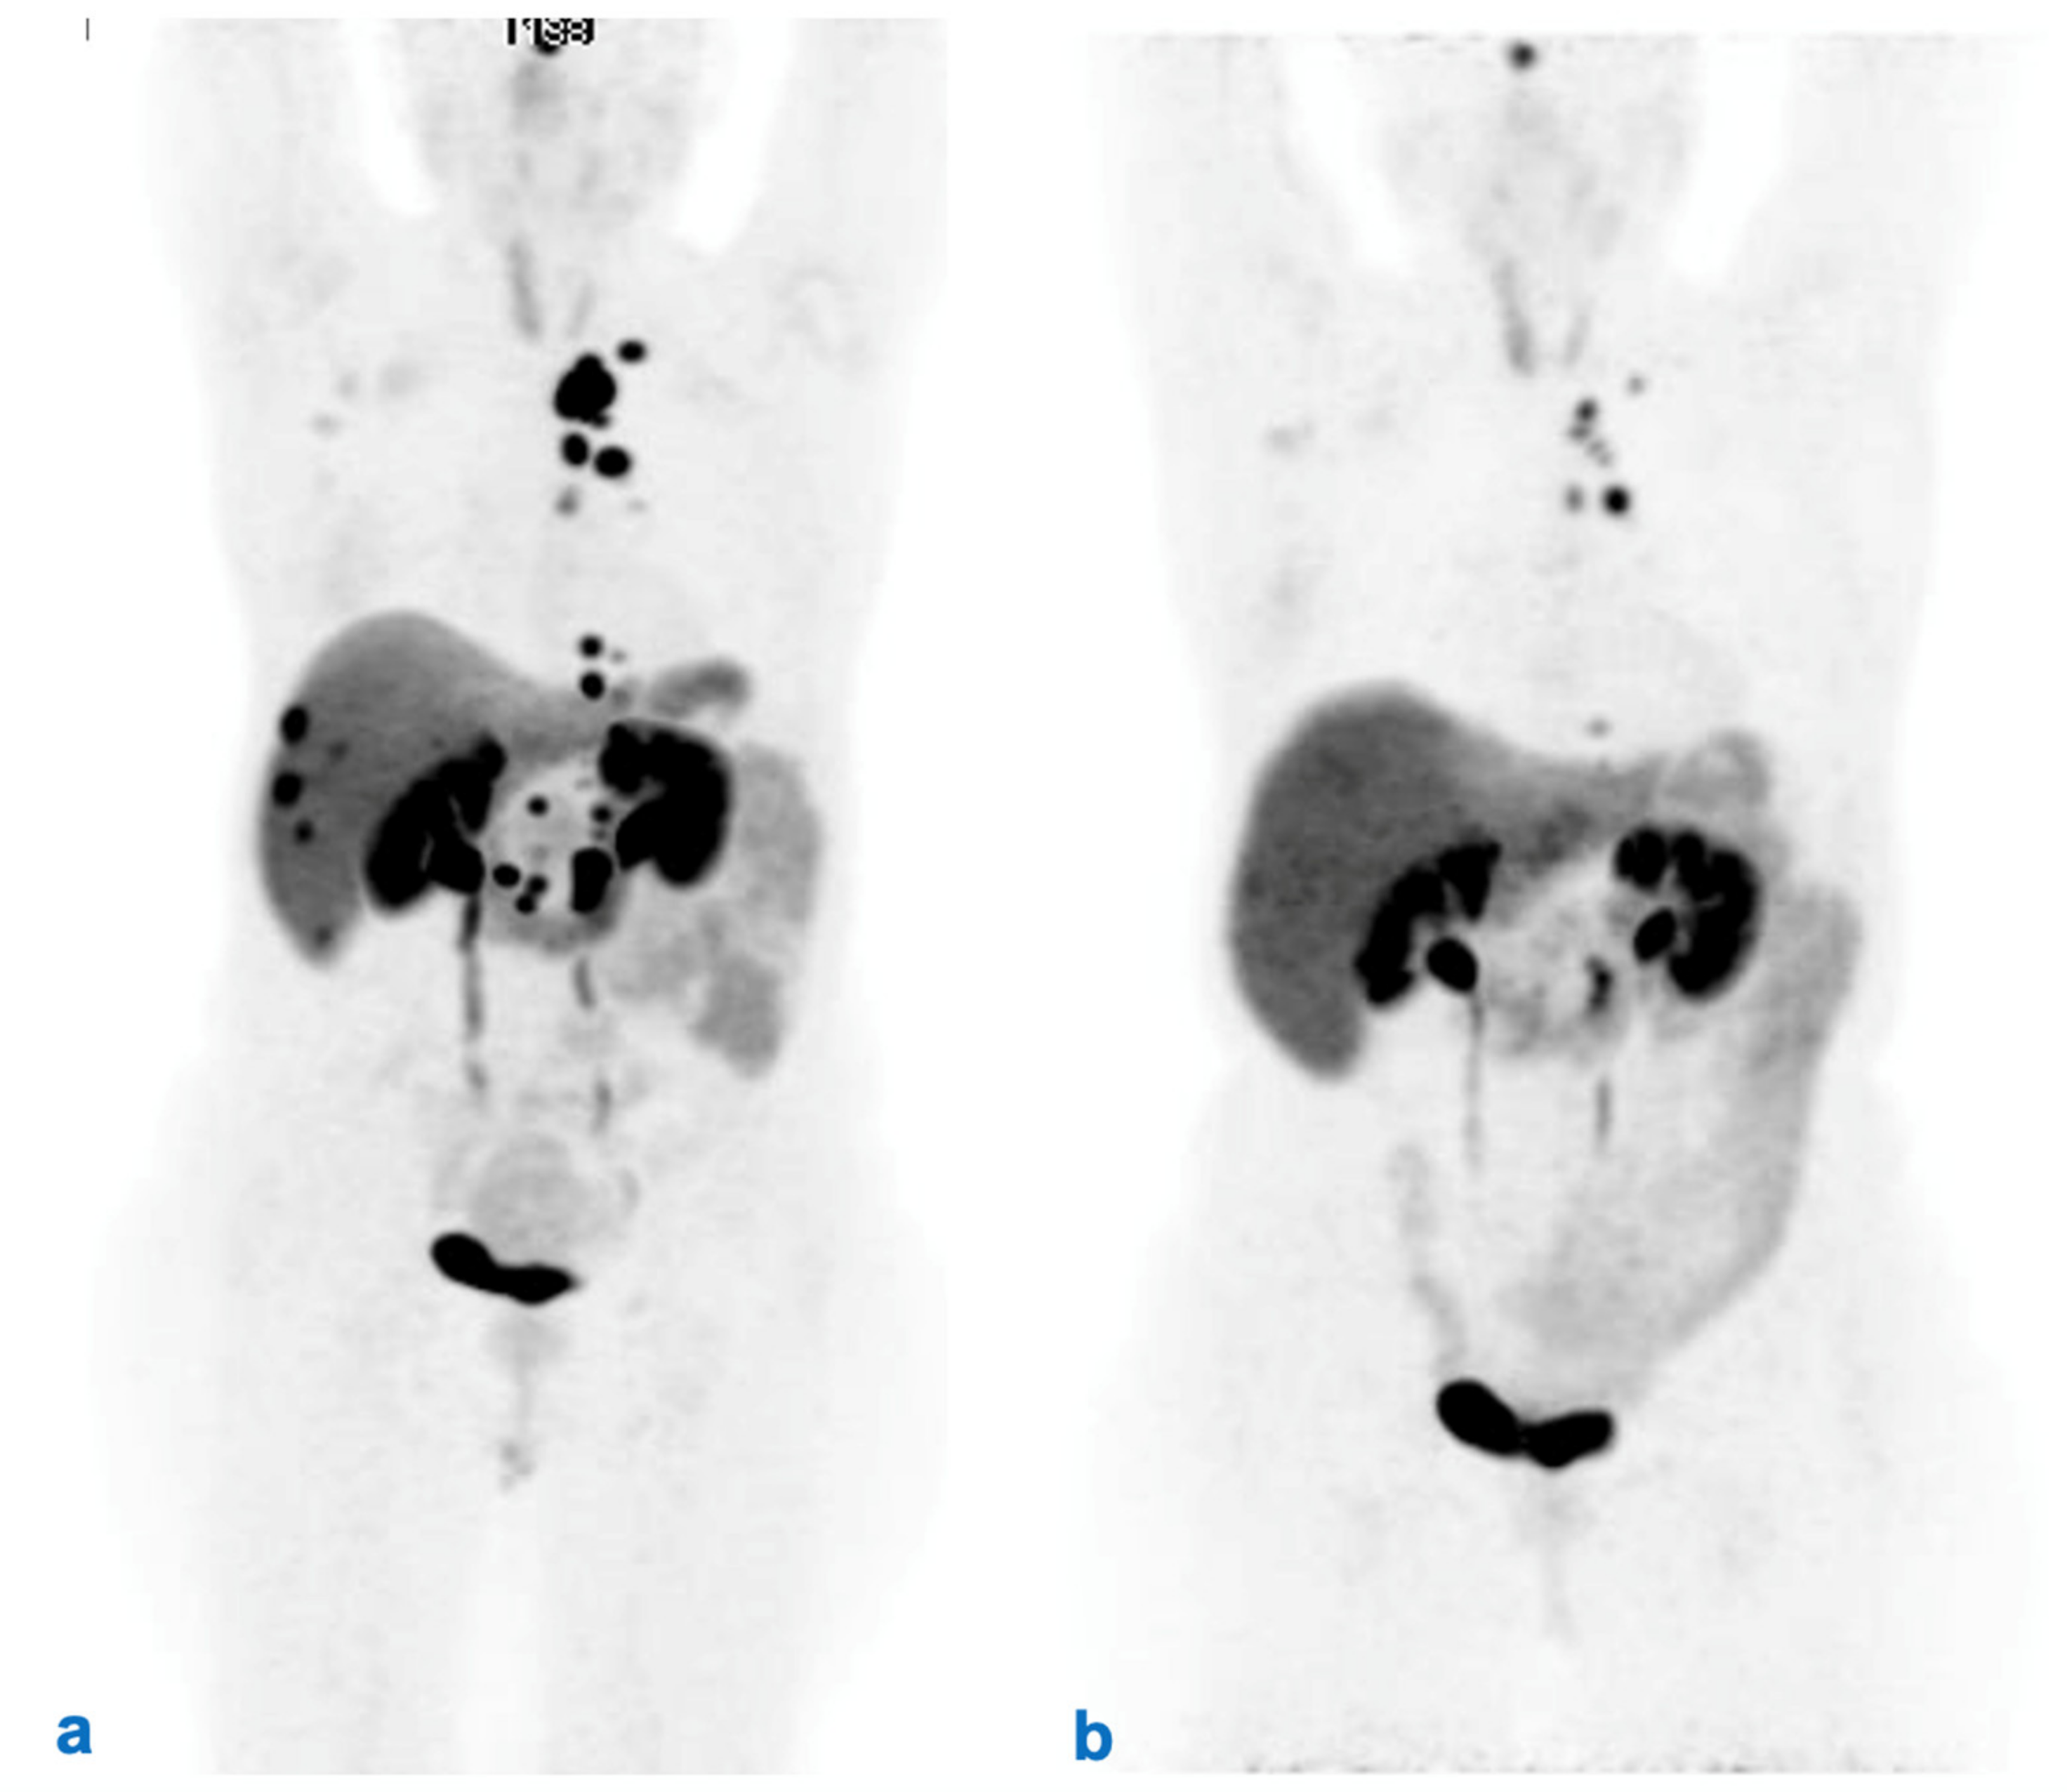

| 10. Evaluation of response (morphological vs. functional and clinical) after RLT | Assessment of tumor response after RLT should carefully consider both morphological and functional imaging. However, the timing of imaging should be correlated with characteristics of the individual tumor. |

| 11. Follow-up after RLT | Follow-up should be patient-tailored and include morphological (CT and/or MRI) and/or functional (PET/CT with radiolabeled somatostatin analogs and/or FDG) imaging and biomarkers, chosen based on the characteristics of the tumor. The timing should be modulated based on prognostic parameters, while strongly considering safety issues. It is suggested to intercalate morphological and functional imaging to reduce the patient’s irradiation dose given the very long follow-up. |